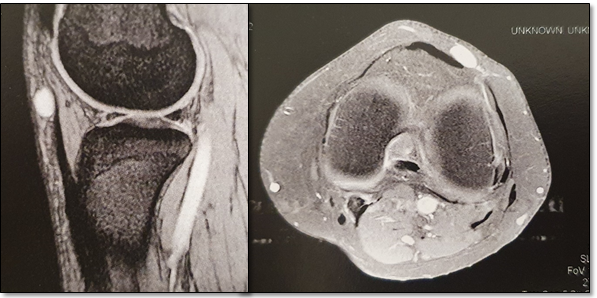

Magnetic resonance imaging (MRI) revealed an ovoid, well circumscribed, mass with low signal intensity in T1 and high signal intensity in T2. Following gadolinium administration, it revealed diffuse and homogenous enhancement (Figure 1).

Figure 1 MRI revealing an ovoid, well circumscribed lesion, with diffuse and homogenous contrast enhancement.